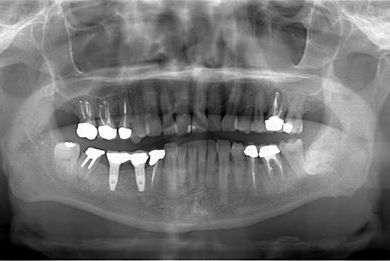

インプラントの症例写真 IMPLANT

インプラント治療+セラミック治療

| 主訴 | 部分入れ歯のバーが舌に当たるため、奥歯2本のインプラント治療を希望。 | ||||||||||||||||||||||||||||||||

| 治療方針 | 右下欠損部分をインプラント治療にて、機能的・審美的回復を行う。 | ||||||||||||||||||||||||||||||||

| 治療内容 | インプラント2本、メタルボンドセラミッククラウン8本、メタルボンドセラミック用土台6本 | ||||||||||||||||||||||||||||||||

| 総治療費 | 1,474,620円 | ||||||||||||||||||||||||||||||||

| 治療期間 | 1年6ヶ月 |